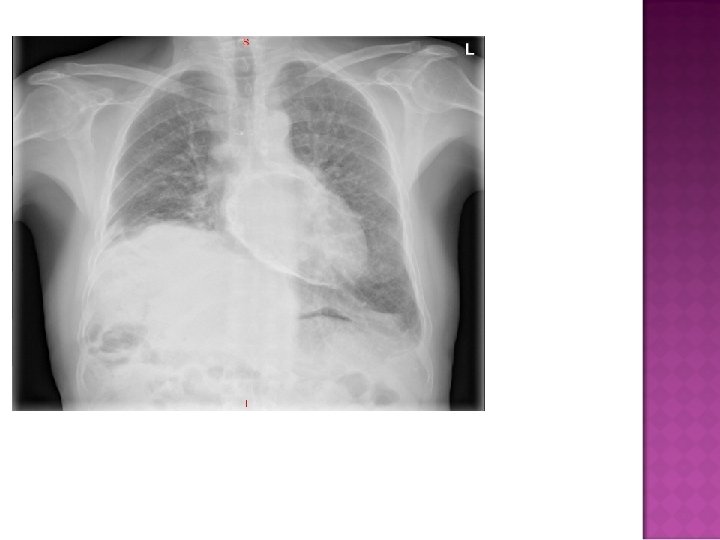

Cardiomegaly due to a massive pericardial effusion. At least 200 m. L of pericardial fluid must accumulate before the cardiac silhouette enlarges.

� Sudden inc in size of cardiac silhouette w/o specific chamber enlargement � Effacement of the normal cardiac borders � Development of a “flask” or “H 2 O-bottle” shaped heart

Normal in patients with acute pericarditis unless pericardial effusion is present Enlarged cardiac silhouette Requires 200 cc of fluid